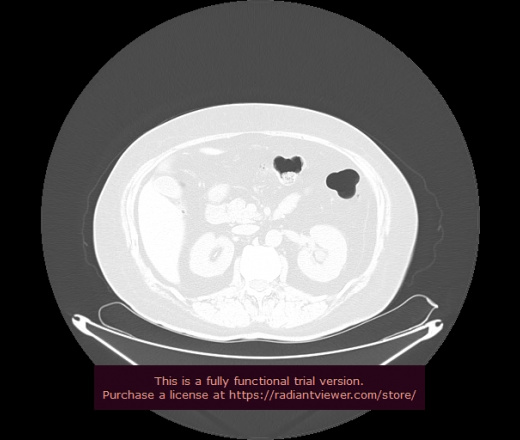

Уважаемые коллеги, если имеется интерес, сможете ли Вы спрогнозировать дальнейшее +-одинаковое течение процесса у 4 данных разных пациентов? Зацепиться где-то можно очень просто, где-то нельзя.